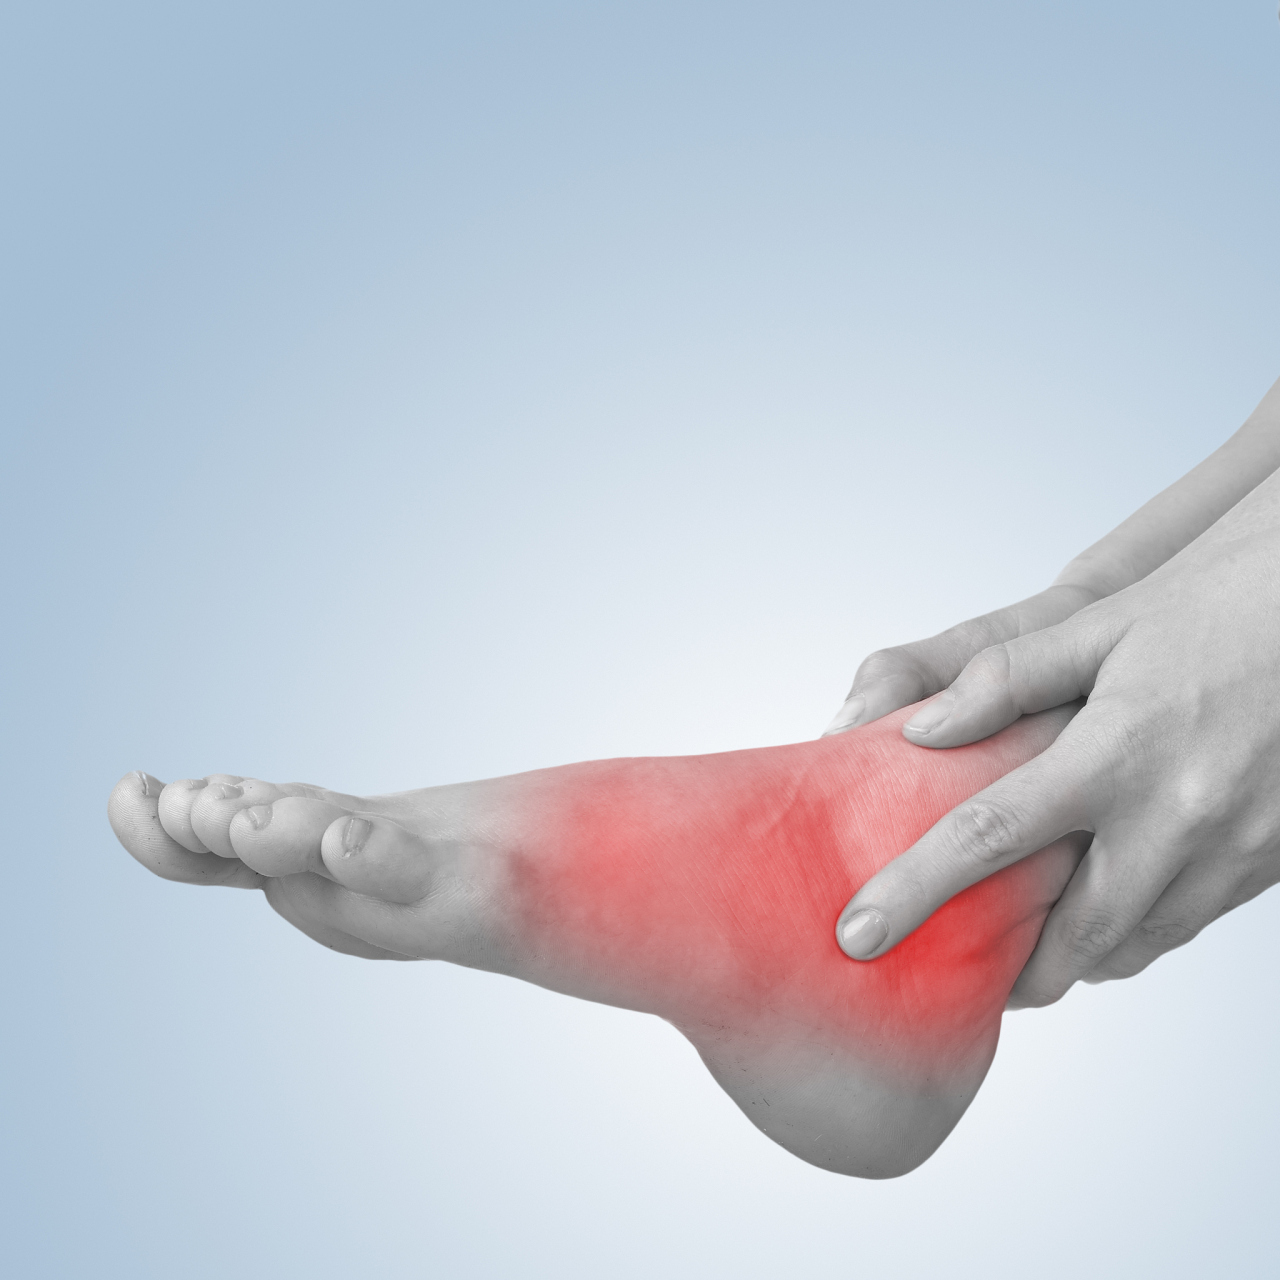

踝关节骨性关节炎,踝关节撞击综合征.

图片尺寸2592x3840